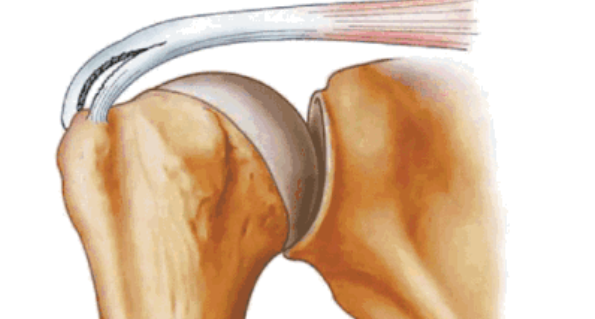

全层撕裂按照范围分为小撕裂:撕裂口<1cm,中撕裂:撕裂口1-3cm,大撕裂:撕裂口3-5cm,巨大撕裂:撕裂口>5cm。高清晰度的MRI是可以测定撕裂范围的。

按照撕裂的形状又分为新月形撕裂、U形撕裂、L形撕裂、倒L形撕裂、巨大回缩性/不可移动性撕裂。想要判断损伤的形状需要在MRI上利用多个平面、多张照片来分析。